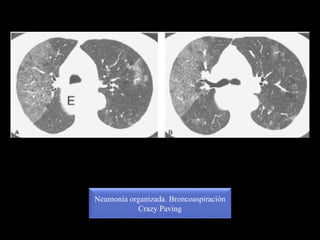

Neumonía organizada. Broncoaspiración

Crazy Paving